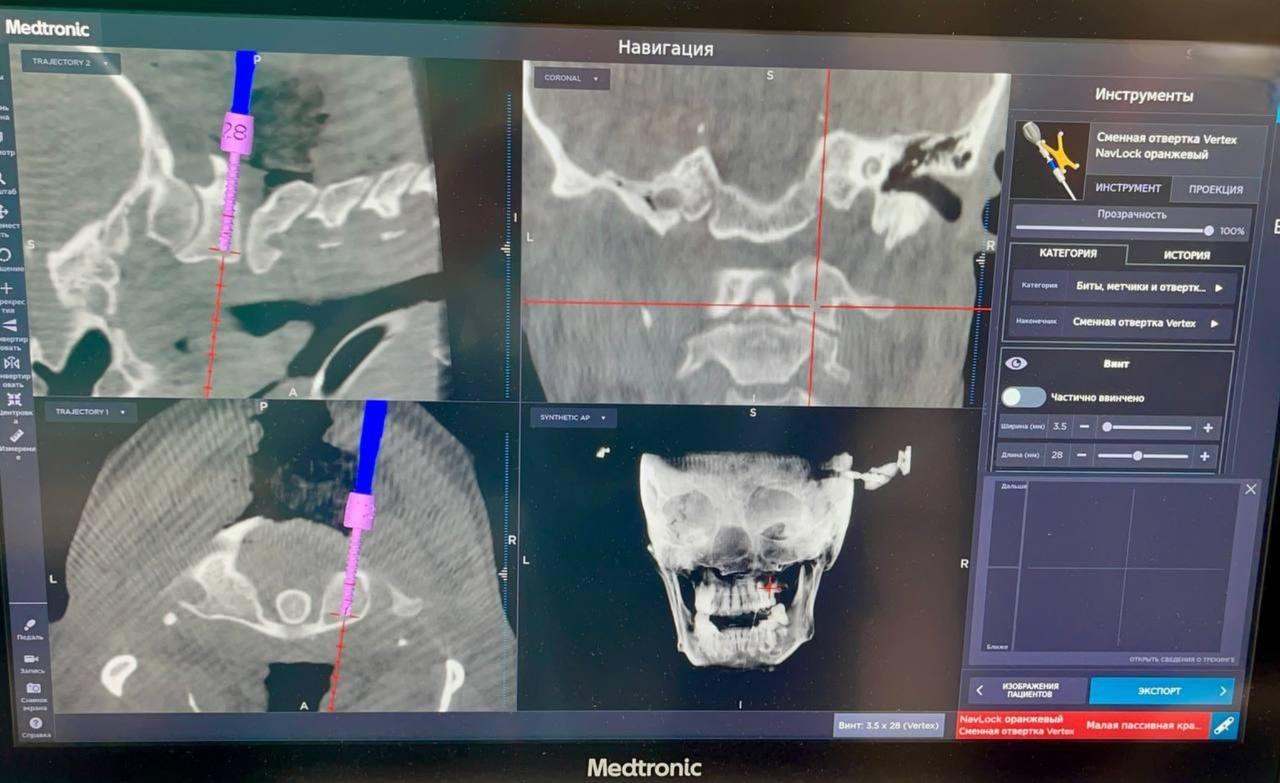

Однако затем врачи зафиксировали смещение костного отломка. Эта нестабильность перелома потребовала хирургического вмешательства для надежной фиксации. Сложнейшую операцию провели в НИИ скорой помощи им. И.И. Джанелидзе.

Хирурги закрепили шейные позвонки специальными винтами. Операция прошла успешно, что позволит надежно и правильно срастить перелом. Уже на следующий день пациентка смогла встать на ноги.